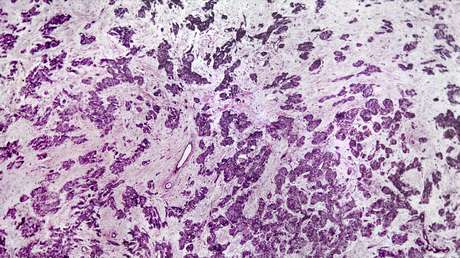

De acuerdo con el estudio, recientemente publicado en la revista Nature, se trata de un nuevo grupo de tumor carcinoide que normalmente deriva de las células del sistema endocrino difuso, bautizado 'supracarcinoide'. El hallazgo fue posible gracias a tecnologías innovadoras de secuenciación que proporcionan información sobre las características moleculares de los tumores, explican los científicos.